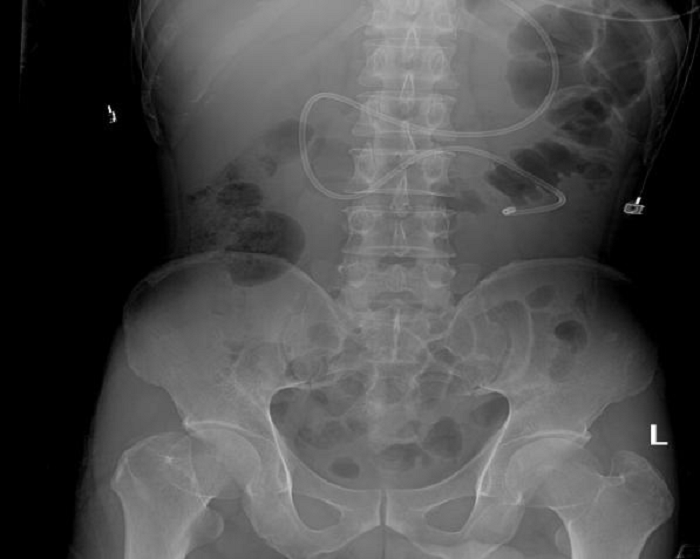

經(jīng)過一系列準(zhǔn)備,根據(jù)超聲顯影,鼻腸管從賁門到通過幽門,動態(tài)調(diào)整徐徐送入空腸,超聲顯示鼻腸管尖端最終到達十二指腸空腸段(圖3、4),整個過程緊張有序,在劉學(xué)松副主任醫(yī)師、普布央金護長及何軍副主任護師的共同努力下,成功為患者置入鼻腸管。

置管過程中患者的各項生命體征平穩(wěn),沒有出現(xiàn)置管并發(fā)癥等情況。床旁超聲引導(dǎo)下鼻空腸管置入術(shù)解決了重癥患者的營養(yǎng)補給問題,同時也彌補了醫(yī)院和科室此項技術(shù)空白。經(jīng)鼻腸管給予腸內(nèi)營養(yǎng)支持治療以來,患者營養(yǎng)狀態(tài)明顯改善,沒有出現(xiàn)胃潴留、營養(yǎng)不耐受等情況。

(圖3、4)

雖然解決了患者營養(yǎng)補給的通路,但該患者存在食管胃底靜脈曲張破裂出血,經(jīng)過消化內(nèi)鏡止血術(shù)后依然存在再出血的風(fēng)險,何軍再次運用超聲技術(shù),可視化評估是否存在再出血,并且可通過超聲計算出血量。最終,患者在醫(yī)護團隊的悉心照顧下,在1周后成功拔出氣管插管,10天后順利轉(zhuǎn)出ICU病房。